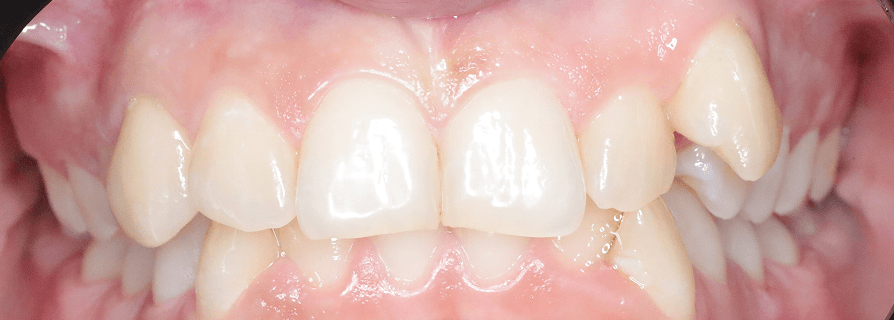

Tratament Interceptiv și Ortodonție Fixă - Dentiție Mixtă

Aceasta este o pacientă de 9 ani pe care am tratat-o în două etape pentru a obține rezultate optime. În prima fază am aplicat tratament interceptiv specializat pentru copii, folosind un disjunctor pentru expansiunea arcadei superioare. Ulterior, am continuat cu aparat fix bimaxilar pentru alinierea perfectă și corectarea mușcăturii.